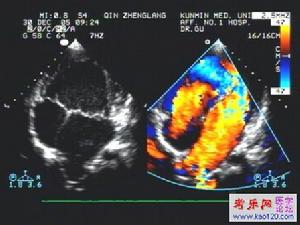

5、彩色多譜勒超聲心動圖:右心室增大,確定狹窄的解剖學位置及程度。

5、超聲心動圖可顯示瓣膜活動及狹窄情況,有無漏斗部肌型梗阻。